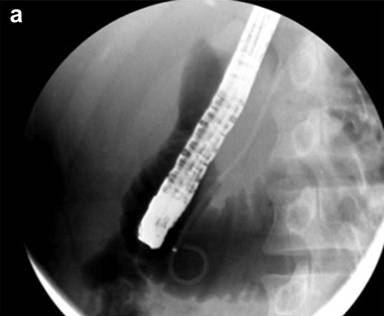

Prophylactic stenting of the pancreatic duct (Figure 2a) has been shown to decrease the risk of PEP in several situations, including SOD, precut sphincterotomy, balloon dilation of the biliary sphincter, ampullectomy, and pancreatic guidewire assisted cannulation of the bile duct [30, 35, 36]. Prophylactic stenting should be considered in all patients prior to performing precut sphincterotomy. This is supported by data showing that the rate of PEP is only 4.3% when precut sphincterotomy for biliary access is performed over a pancreatic stent [37]. It is also thought that the stent may help delineate the ductal anatomy and assist in selective cannulation of the biliary orifice after precut sphincterotomy. There is also data to suggest that pancreatic duct stenting may be protective in all patients undergoing ERCP [38]. However, the standard of care for prophylactic stenting remains in patients at high risk of PEP. This is also corroborated by a cost-effectiveness analysis, which demonstrates the superiority of prophylactic stenting in patients at high risk of PEP compared to stenting all patients or no patients undergoing ERCP [39].

Figure 2. Pancreas stenting (a.) in high risk cases and wire guided approaches (b.) are technical manoeuvres which minimize the risk of PEP. |

Cannulation Techniques

Cannulation using a guidewire (Figure 2b) rather than contrast-directed cannulation is considered a valuable technique in preventing PEP. This enables access to the desired duct using a soft-tipped guidewire, while avoiding contrast injection into the pancreatic duct. It is also thought that inadvertent advancement of a guidewire into the pancreatic duct may be less traumatic to the pancreas than contrast opacification. Wire-guided cannulation first received considerable attention when a prospective study randomized 400 patients to wire-guided cannulation versus conventional contrast directed cannulation. Cannulation success rates were similar, but no PEP developed in the guidewire group, whereas PEP occurred in 4% in the contrast group (P<0.01) [44]. Since then, several studies have indicated that wire-guided cannulation reduces the risk of PEP. Subsequent large randomized trials have consistently demonstrated PEP rates of 2-9% in wire-guided versus 10-17% in contrast guided ERCP [44-46], which has also been supported by several meta-analyses [47-50]. However, there is some heterogeneity in the data [47] and the wire-guided technique has come under scrutiny as two recent prospective studies have not shown a reduction in rates of PEP [51, 52]. There may be several reasons for the mixed data on wire-guided cannulation. First, the endoscopists performing the procedures in these studies may have variable experience with one particular technique, which can potentially bias the data. The second reason is that “wire-guided cannulation” is not a single technique, but rather a method of cannulation that can be performed in many different ways. Pure wire-guided cannulation involves introducing the wire into the biliary orifice, while keeping the tip of the sphincterotome in the duodenal lumen. Another variation of wire guided-cannulation is when the tip of the cannula is inserted into the common channel and the wire is gently probed back and forth at varying angles until the biliary orifice is entered. The wire can be controlled by the assistant or by the physician. A hybrid method also exists, where the desired duct is first opacified with contrast, then the guidewire is used to access the duct [30]. Most advanced endoscopists use a combination of these methods, making generalization of studies on wire-guided cannulation problematic. However, based on the abundance of favorable data, it is reasonable to conclude that the wire-guided technique should be considered a first-line modality for cannulation.